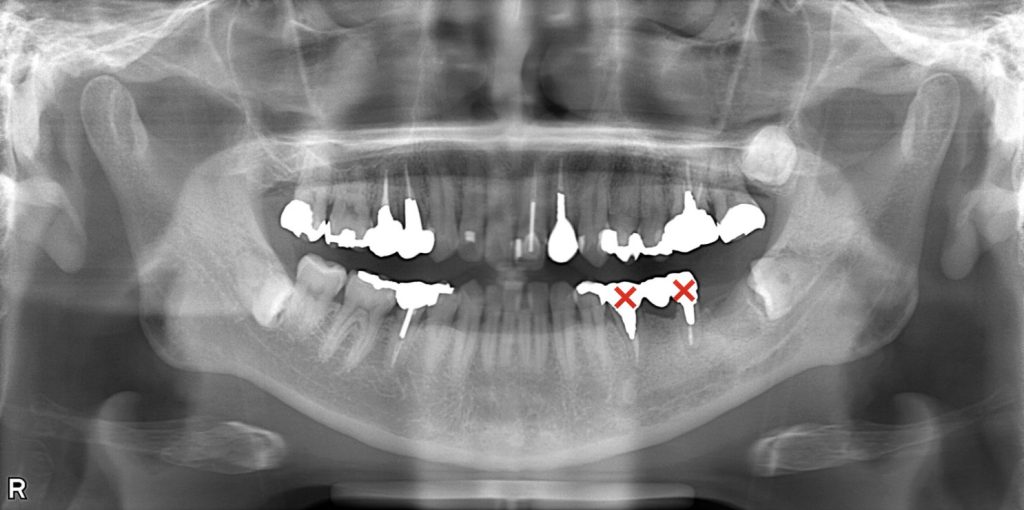

レントゲン画像(抜歯前)

レントゲン画像(インプラント埋入後)

以上より、左下5・左下6の抜歯後治療として、

**インプラント・ブリッジ・義歯(入れ歯)**のいずれかの補綴治療が必要と判断。

治療計画としては、患者様の身体的・金銭的負担の最小化と機能回復の両立を目的に、

・最も咬合力が集中する左下6・左下7部位にインプラント2本埋入

・左下5部位はカンチレバー構造を応用し、インプラント本数を最小限に抑制

する設計とした。